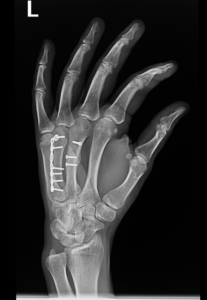

if the fracture is displaced, surgery may be needed to put the bone back into the correct position and fix the bone with Plates & screws or nails for adequate healing to occur.

- Hand Fractures.

- Open or compound fracture – the skin overlying the fracture is also broken. Displaced or nondisplaced fracture – treatment options depend on whatever the broken bone is displaced or nondisplaced